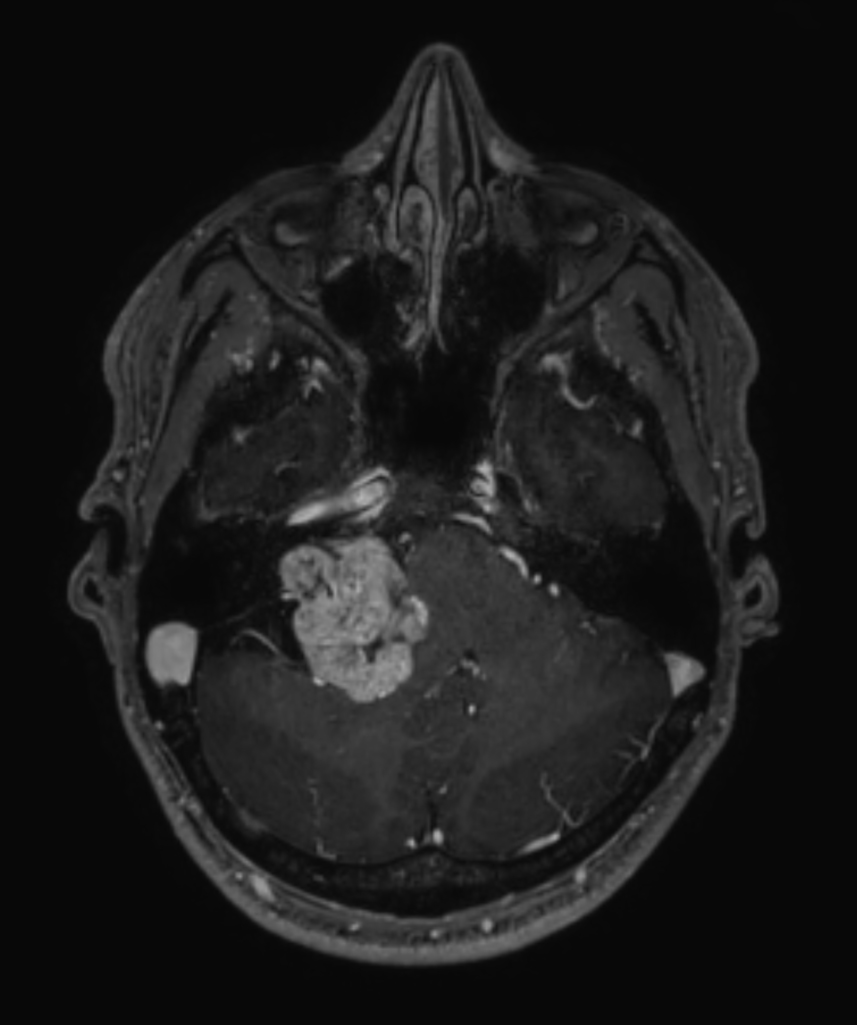

Patient with a brain (IAC) lesion. Compressed SENSE is used to shorten the scan time of the high resolution clinical scans, whilst MultiBand SENSE is used to reduce the scan time of the functional (DTI) scan.

Axial 3D T1w TFE BrainVIEW with gado (reformat)